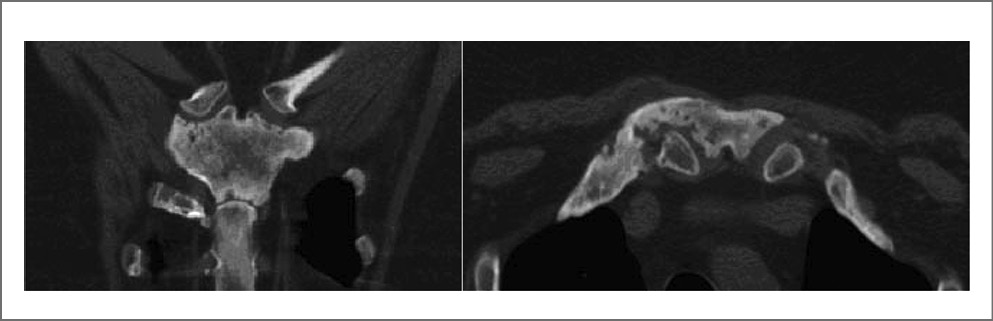

Поскольку в развитии ОАПГК существенную роль играет остеит, диагностическую ценность имеют рентгеновские методы, особенно компьютерная томография (КТ) [2, 17, 18]. Первоначально выявляются литические изменения медиального отдела ключицы и периостальное образование костной ткани, быстро формируется оссификация реберно-ключичной связки. Затем присоединяются признаки артропатии манубриостернального, грудино-ключичных и грудино-реберных суставов (эрозии и расширение, затем сужение щели, остеосклероз сочленяющихся отделов); рис. 4, 5. Очаговая деструкция грудины, ключиц, передних отрезков ребер, а также пролиферация костной ткани в виде периостита, гиперостоза костей, их неравномерного склероза напоминают картину остеомиелита.

Рис. 4. КТ передне-верхней части грудной клетки пациентки П., 54 года, с ОАПГК (синдром SAPHO). Слева (коронарная плоскость): эрозирование сочленения рукоятки с телом грудины, а также сочленений рукоятки с ключицами (слева с расширением щели); неравномерный остеосклероз рукоятки. Справа (аксиальная плоскость): деструкция и частичный анкилоз грудино-ключичного сочленения, расширение (гиперостоз) и перестройка костной структуры медиального отдела правой ключицы (собственное наблюдение [1]).